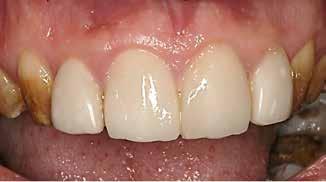

Klinisk undersøgelse viste emaljehypoplasier og hypomineralisering på 1+, +1, 2-, 1-, -1 og -2 (Fig.1). Hun havde Angle klasse II, pladsmangel i begge kæber og agenesi af -5. Der var isninger ved spisning og tandbørstning. Fundene var forenelige

BAGGRUND – Denne kasuistik beskriver en patient, hvor der blev valgt protetisk behandling i ung alder.

PATIENTTILFÆLDE – En niårig pige havde stort behandlingsbehov og smerter fra tænderne på grund af tandudviklingsforstyrrelse. Der var flere gange forsøgt restaurering med komposit, som ikke fungerede. Laminater i feldspatkeram blev valgt for at fjerne mindst mulig tandsubstans, øge holdbarheden på restaureringerne og forbedre æstetikken. Patientens motivation, meninger og kooperationsevne var vigtige for behandlingsvalget, da behandlingen var tidkrævende og til tider udmattende for en ung patient.

KONKLUSION – Resultatet var vellykket og medførte forbedret livskvalitet. Protetisk behandling med adhæsiv teknik kan være et godt behandlingsalternativ for børn og unge på ret indikation.